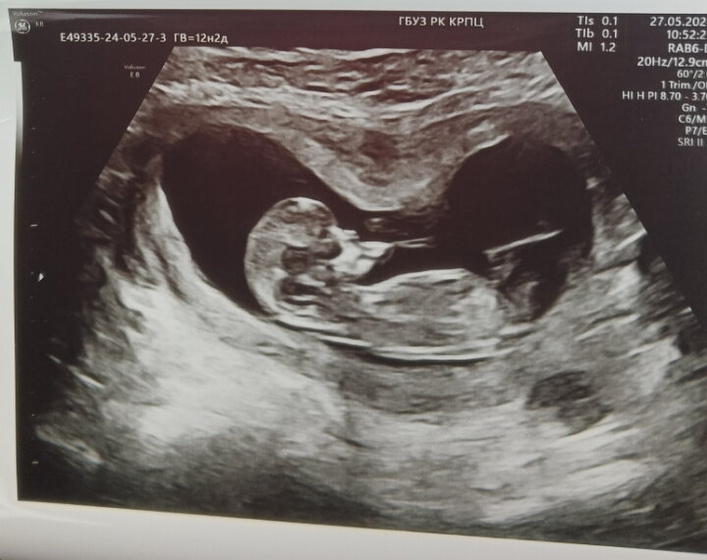

Скрининг в12. 2

Ктр 57 мм на 12.2 недели.

Бпр 18 мм на 12.6

Окружность головы 66мм на 12.4

Твп 1.5 мм

Носовая кость 2.4 мм

Пульс 170

Предложение хореона

По передней стенке